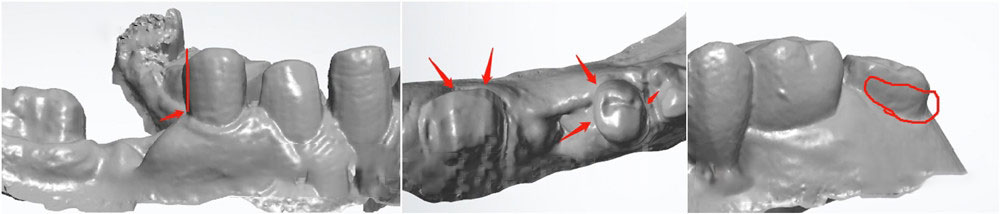

2. Remove undercuts

Please try not to leave undercuts after preparing teeth, or at least not big undercuts. In many situations, doctors ask for bridges, but they send cases with very big undercuts. If we just block so many big undercuts, doctors may find the crowns very loose (for easier fitting). And patients could suffer from food trap over time. This could also cause gum infection.

big undercuts dental preps